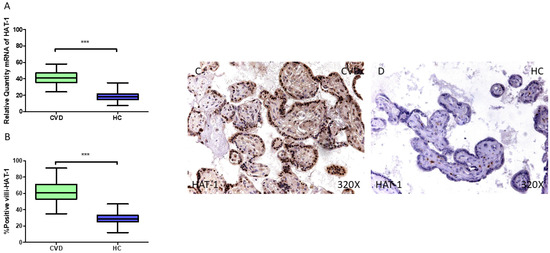

3.1. Placentas of Women Who Undergo Chronic Venous Disease During Pregnancy Display Decreased Expression of Key Circadian Markers

3.2. The Placentas of Women with Chronic Venous Disease During Pregnancy Show Evidence of Altered Epigenetic Markers